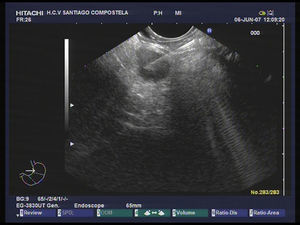

Ultrasonografía endoscópica (USE)La USE aporta imágenes de alta resolución del parénquima pancreático por lo que puede distinguir lesiones de hasta 2–3mm de diámetro. Los TNE generalmente son tumores pequeños (fig. 1), de hecho los insulinomas suelen ser inferiores a 1cm, y solo los no secretantes o no funcionantes suelen ser voluminosos (más de 3cm). Las lesiones son hipo o isoecogénicas, estando bien delimitadas, pareciéndose a las adenopatías; cuando tengan aspecto quístico o irregular deberá establecerse el diagnóstico diferencial con los tumores mucinosos y con el adenocarcinoma14 (fig. 2).